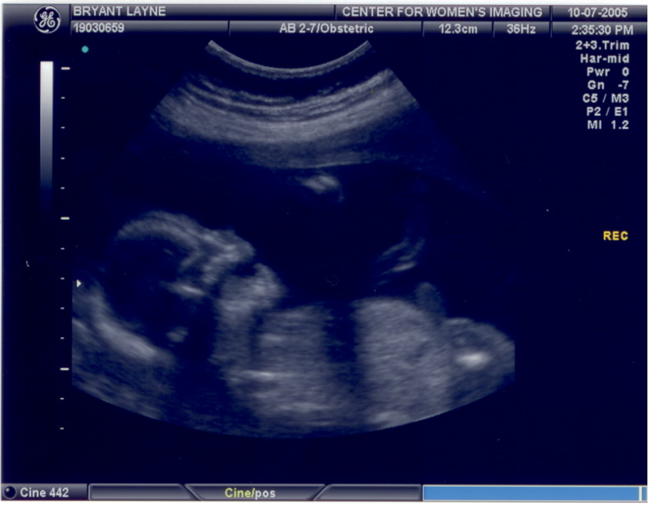

Caroline's Second Ultrasound

These pictures were taken on October 7th at about 20 weeks.